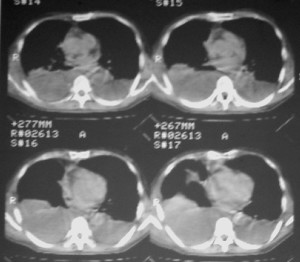

m ,60岁,右上肺ca术后一月。

右侧肺癌术后:肝内可见多个大小不等的低密度结节影。腹腔及双侧胸腔大量积液。考虑:肺癌并胸膜及肝脏转移。

腹水,肝及右肾多发低密度影。考虑转移。

肝及右肾转移瘤,双侧胸水

右肾及肝内多发转移瘤,胸水。

1、右肺癌术后改变。2、双侧胸水、腹水。3、多发性肝囊肿,右侧肾囊肿。

肺癌术后 。双侧胸水 纵隔 胸膜 肝脏转移